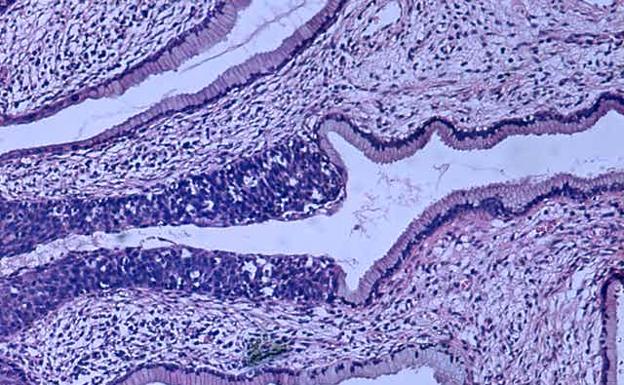

Más de la mitad de los países han incorporado la vacuna frente al VPH en sus programas de vacunación infantil. Sin embargo, la cobertura para la pauta completa de vacunación no alcanza el 20%